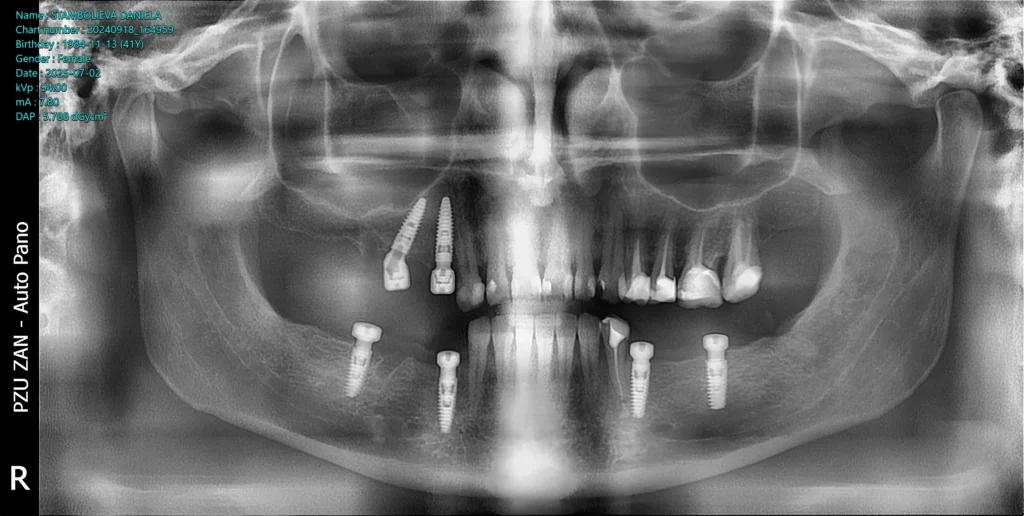

After the examination and the analysis, the therapy plan was full mouth reconstruction with dental implants and zirconia crowns and bridges. The remaining roots were extracted and six dental implants were placed using a surgical guide and digital workflow.

After the healing period of 6 months, the teeth were prepared and a prototype smile with provisional teeth was placed. After the analysis of the prototype smile, we made all the changes need to provide this patient with this new beautiful smile with zirconia crowns and bridges over the dental implants.